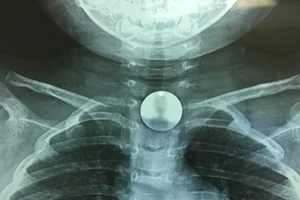

Bé 6 tuổi nuốt đồng xu vào thực quản

15/03/2024 05:58